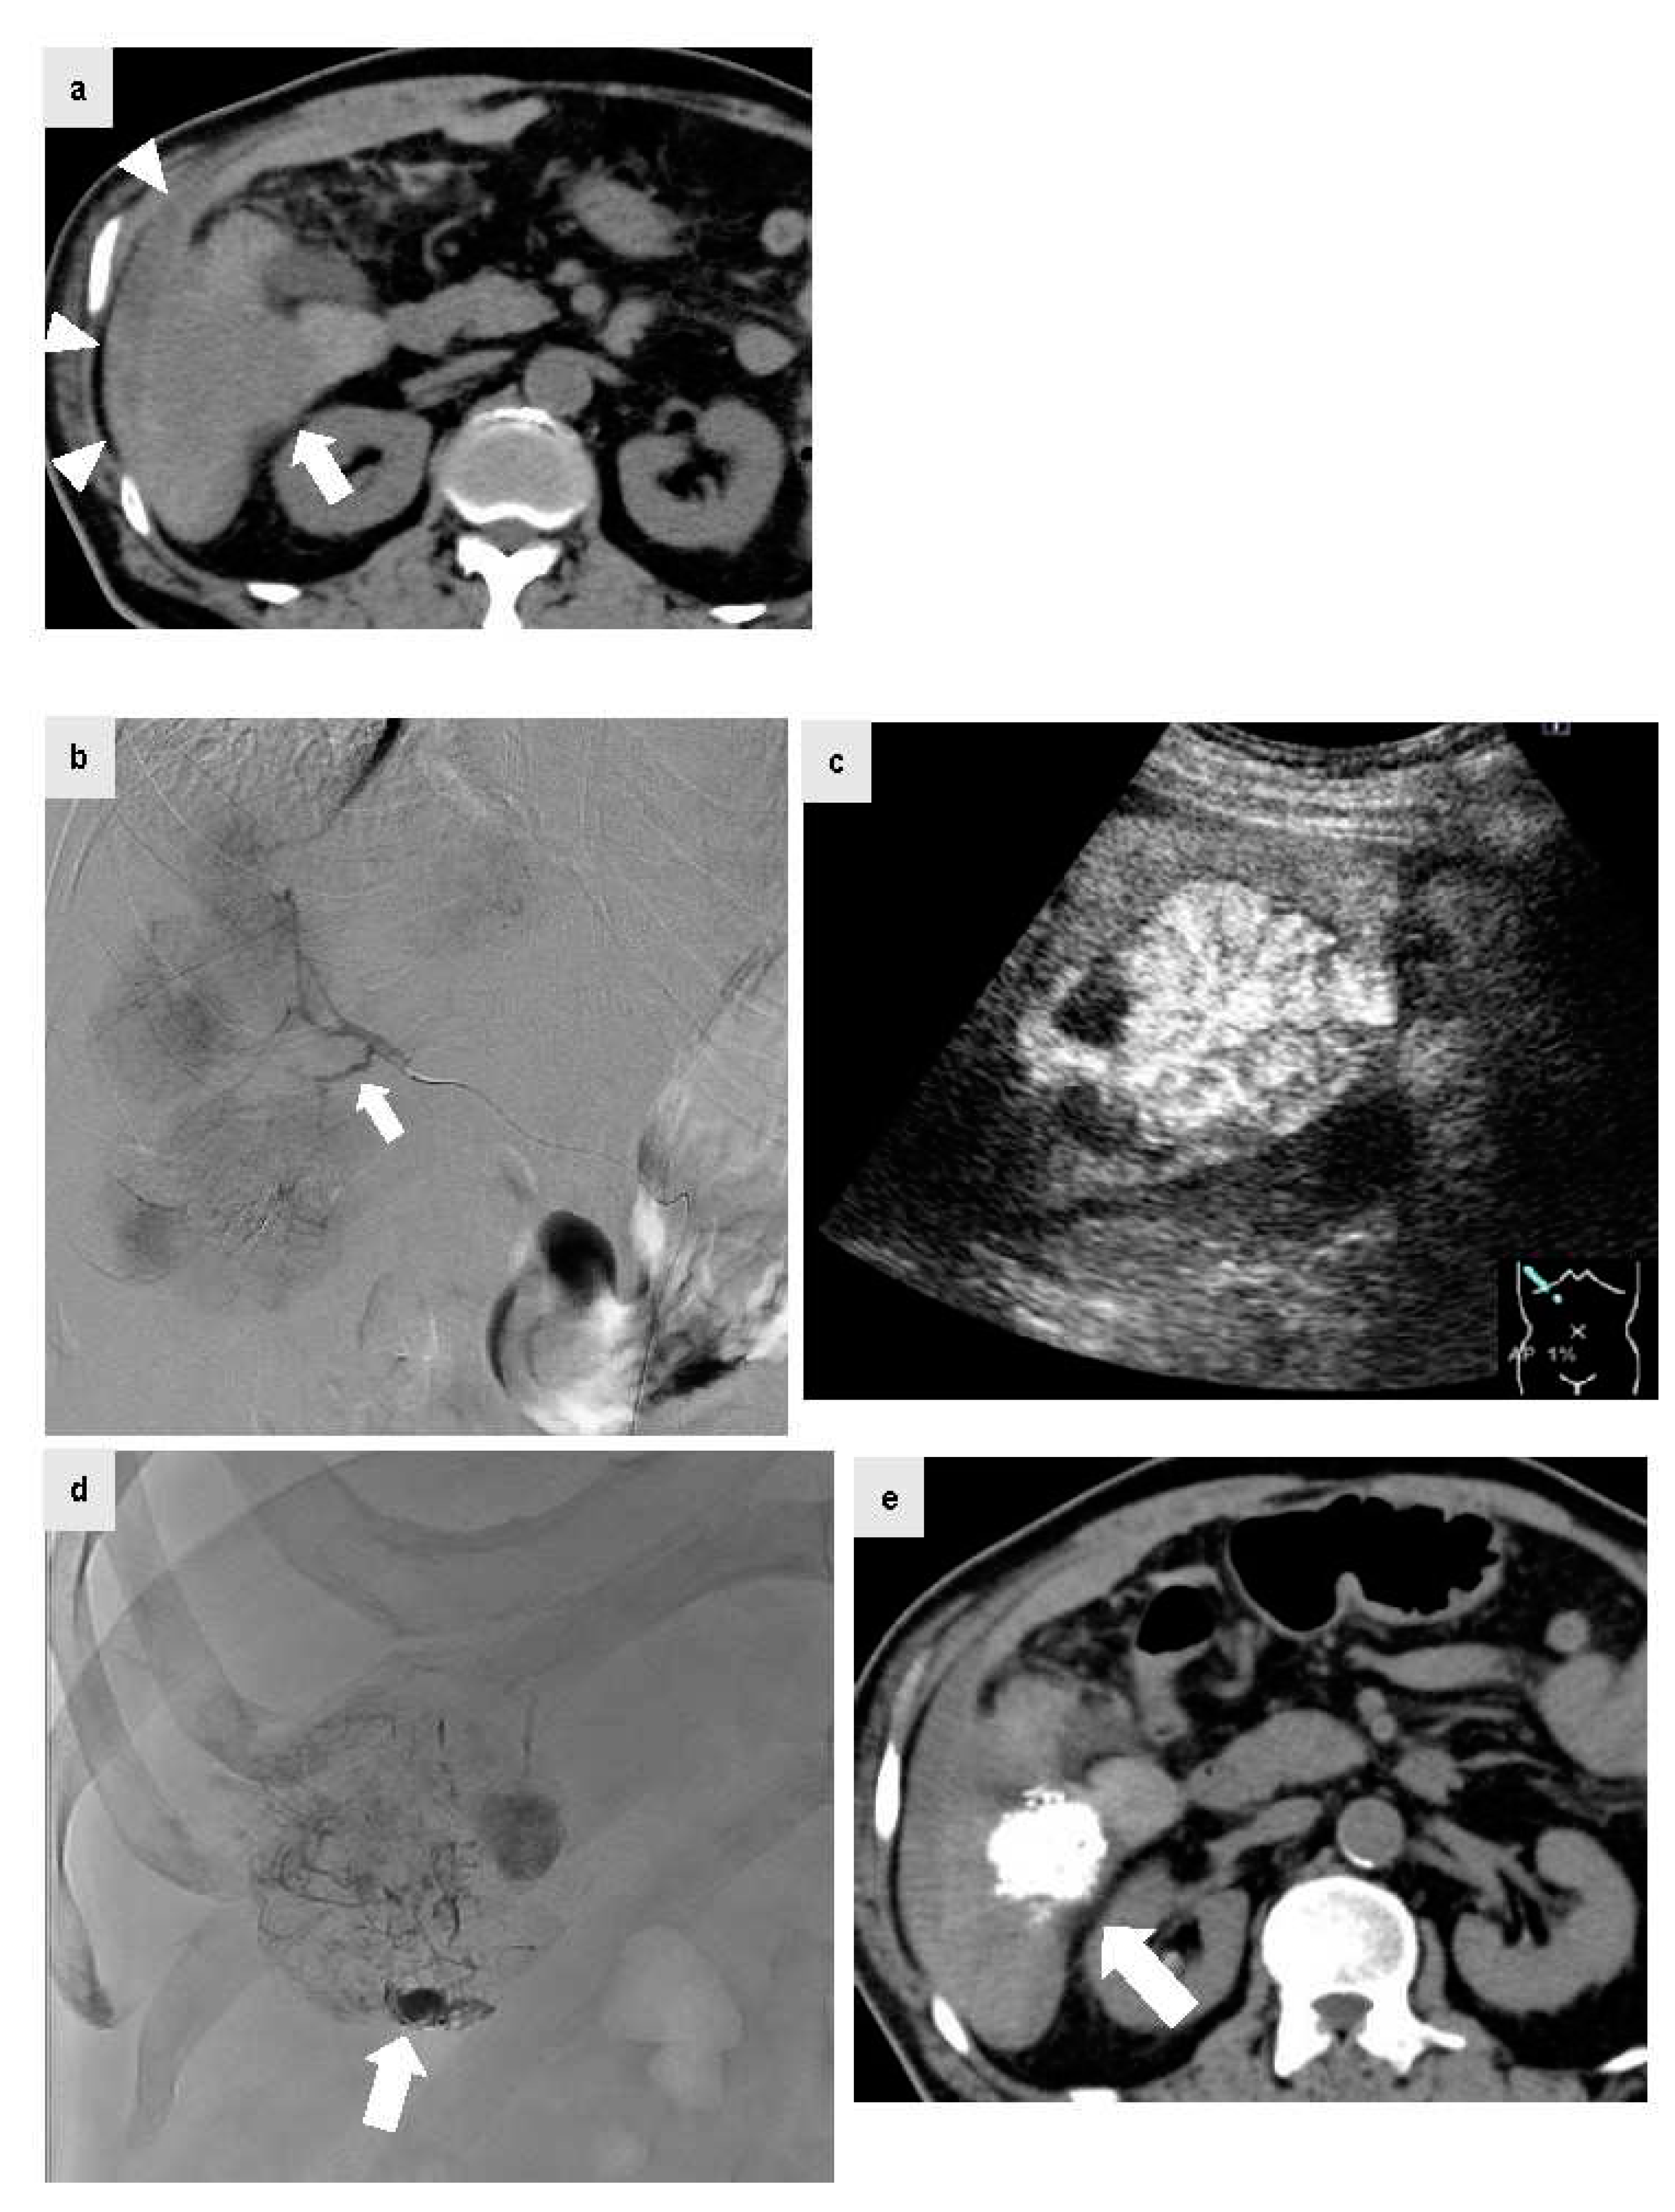

The patient was a male in his 70s with non-alcoholic steatohepatitis-related cirrhosis who visited the emergency department for a chief complaint of acute upper abdominal pain during a period of oral administration of lenvatinib for HCC and multiple bone metastases. At the visit, plain CT was performed because anemia of Hb 9.0 g/dl with blood pressure 80/60 mmHg and renal failure with Cr 2.54 mg/dl were confirmed. Since high density fluid collection (Figure 3a, arrow head) was confirmed on the S6 liver surface contiguous HCC by plain CT (Figure 3a, arrow), HCC rupture was suspected and urgent abdominal angiography was performed. IAUS was then performed frequently to reduce the amount of iodinated contrast agent as much as possible because the patient had renal failure, and a microcatheter was extended to the A6 culprit vessel confirmed by CT. Digital subtraction angiography was performed from the A6 culprit vessel. The tumor staining was confirmed, but no clear extravasation was found. The microcatheter was peripherally inserted (Figure 3b, arrow) and IAUS was performed. IAUS showed the enhanced tumor protruding from the surface of the liver (arrow), and surrounding hematoma (Figure 3c). TACE using ELE and Gelpart® was performed at the same site. During TACE, significant accumulation of Lipiodol® was confirmed in the vascular lake of the tumor on the caudal (Figure 3d, arrow), and this was thought to be a site of HCC rupture. After TACE, IAUS was performed again at the site and showed elimination of contrast enhancement. Plain CT after TACE showed accumulation of Lipiodol® in the HCC (Figure 3e, arrow). After TACE, blood pressure was stable with no rebleeding, and at 3 days after TACE the Cr level had improved to the normal range. Concomitant use of IAUS enabled reduction of the amount of contrast agent to 9 ml in abdominal angiography.